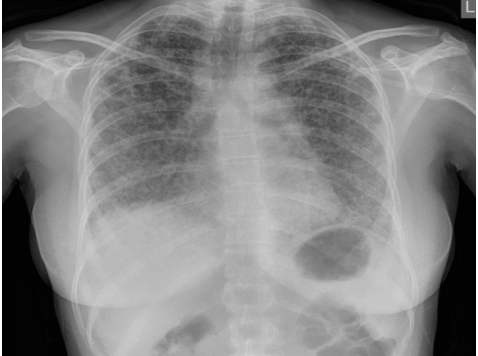

What is the CXR showing?

Reticular shadowing- looks course, nodular type pattern unlike consolidation/ pulmonary oedema

“Reticular nodular” is typical of a fibrotic lung condition

Then do high resolution CT scan